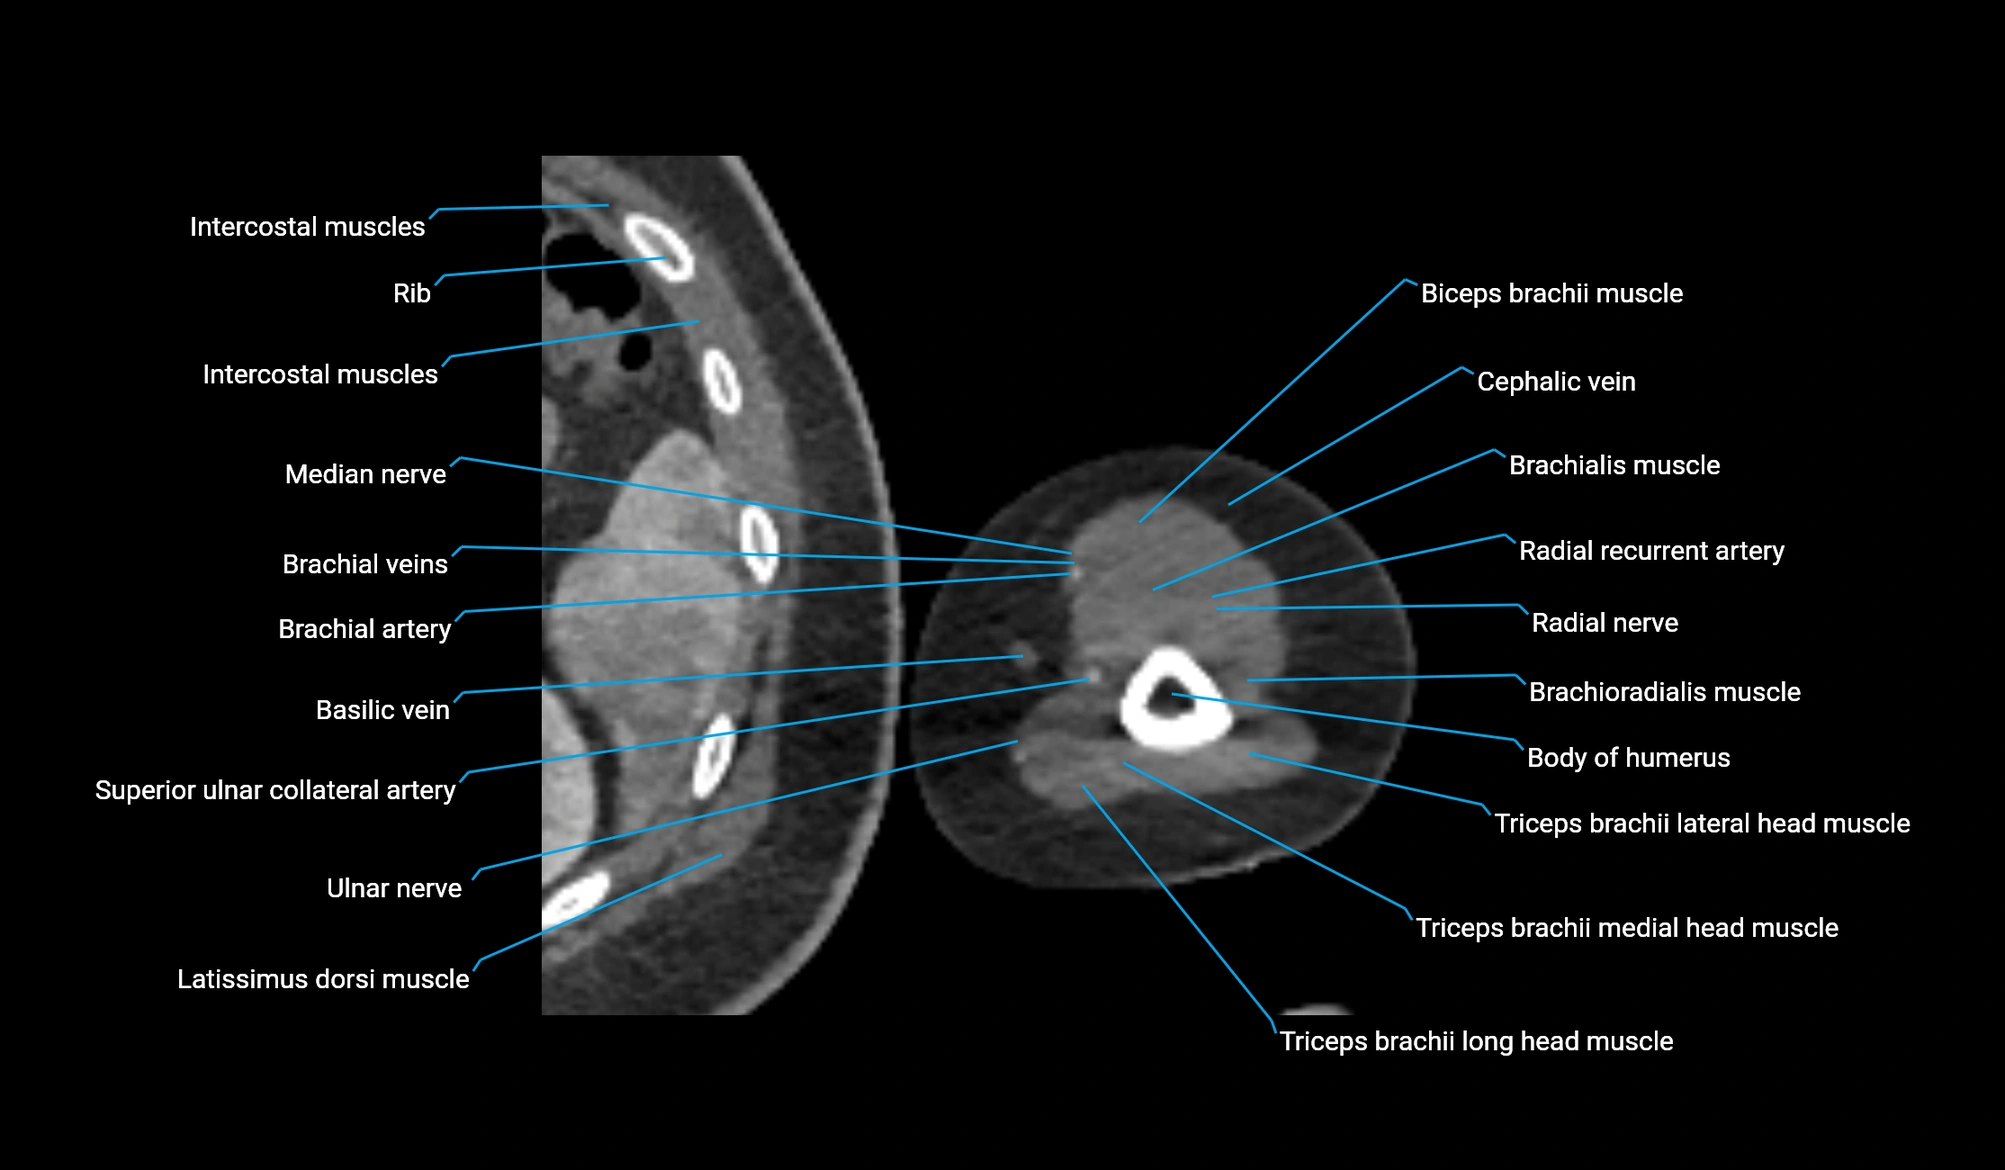

- Biceps brachii muscle

- Brachialis muscle

- Brachioradialis muscle

- Body of humerus

- Cephalic vein

- Brachial artery

- Basilic vein

- Median nerve

- Radial nerve

- Ulnar nerve

- Long head of triceps brachii muscle

- Lateral head of triceps brachii muscle

- Medial head of triceps brachii muscle

- Radial recurrent artery

- Latissimus dorsi tendon